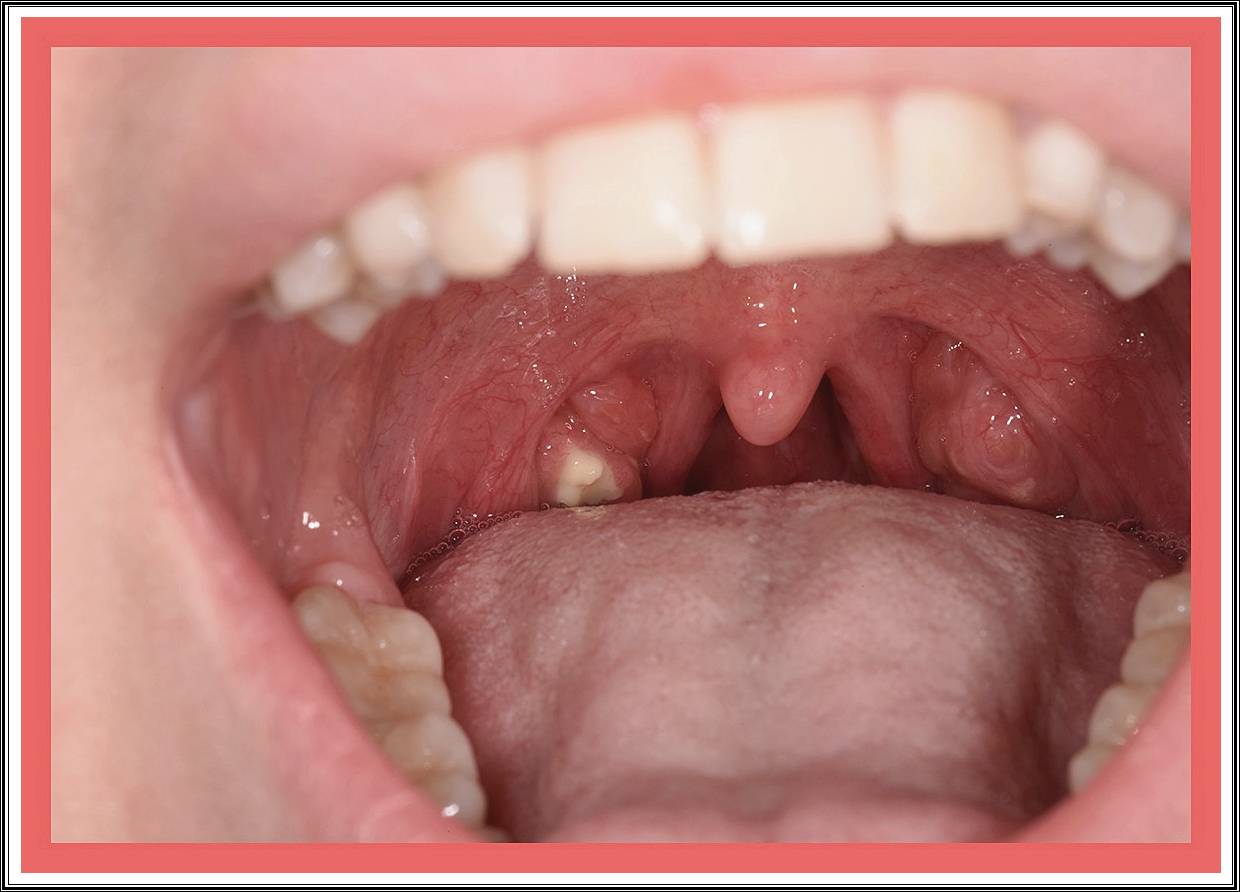

편도결석(tonsillolith)은 편도선의 틈새에 음식물 찌꺼기, 점액, 죽은 세포 등이 쌓여 굳어진 덩어리입니다.

흰색 또는 노란빛을 띠며, 크기는 좁쌀 정도에서 콩알만 한 크기까지 다양합니다.

음식이 목에 닿을 때 찌릿한 느낌이 든다. - 편도 표면에 흰색 점이 보인다

거울과 손전등으로 확인 시 작은 알갱이가 보인다. - 잦은 편도염

편도 표면에 작은 흰색 알갱이나 덩어리가 보이면 결석일 가능성이 큽니다. - 혀압자나 면봉 사용